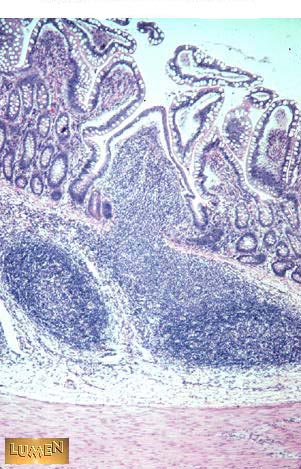

What is the frequency of contracting segments in this organ.

Answer

8-9/min